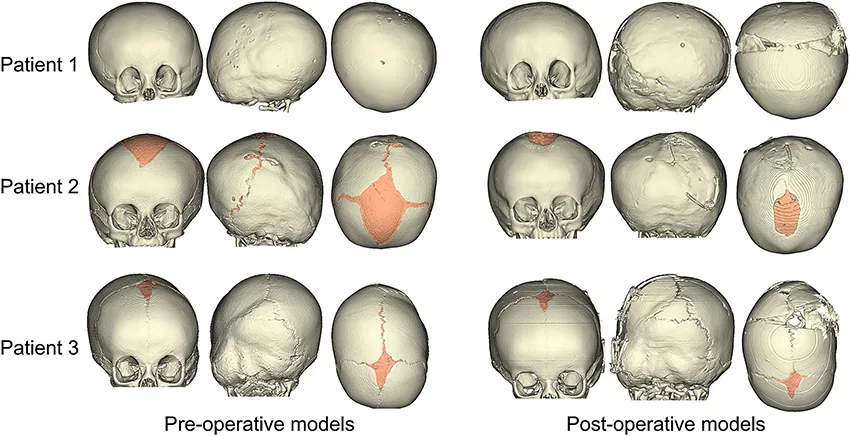

3 例因颅骨形态异常的 LC 患者在英国伦敦大奥蒙德街医院颅颌面外科接受了弹簧辅助颅成形术,并在术前和术后进行头部 CT 扫描。将 CT 图像导入 Simpleware ScanIP 软件中重建这两个不同阶段的颅骨,经过分割和处理以确定颅骨至上颌骨及骨缝结构的骨骼。

在 Simpleware FE 中采用结构化的 3D 四面体单元生成颅骨的有限元(FE)模型,对不同的解剖区域赋予合适的材料属性建模。在对颅骨模型进行截骨之前,通过使用热膨胀系数在 MSC Marc 中近似模拟术前成像和手术之间的颅骨生长。将颅内体积(ICV)作为表示不同阶段颅骨大小的参数,包括在 Simpleware ScanIP 中通过选择颅顶内表面进行术前CT重建。

通过在 Simpleware ScanIP 中追踪手术保留的可见痕迹估算术中 ICV,以此复制手术时的颅骨截骨。然后重新划分截骨的颅骨结构,使用 MSC Marc 中的弹簧/阻尼器连接元件模拟弹簧植入,展示手术和术后 CT 扫描的差异。

重建的颅骨模型展示了术前 CT 时的颅内腔形态,对三名患者的模拟结果进行对比。FE 模型和从 CT 获得术后颅骨模型的分析显示额骨和颞骨的表面偏差率相对较低,在被弹簧扩张的后颅骨上表面偏差增大。